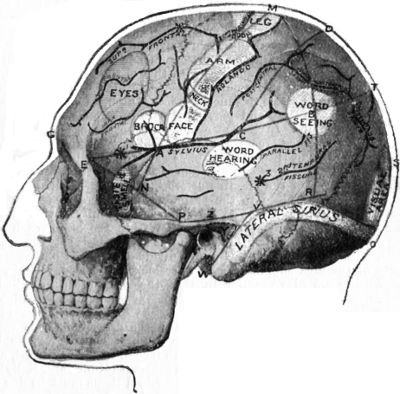

| 179. | Relations of the Motor and Sensory Areas to the Convolutions and to Chiene's Lines | 330 |

| 181. | Chiene's Method of Cerebral Localisation | 336 |